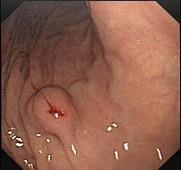

问题 患者,男,59岁,上腹不适2周,查体:心肺腹未见异常。电子胃镜图片及超声内镜如下,进一步要做的最佳治疗方案为 ( )

选项 A.电子胃镜下切除 B.外科手术切除 C.电子胃镜联合腹腔镜切除 D.随访观察 E.口服抗肿瘤药

答案 C